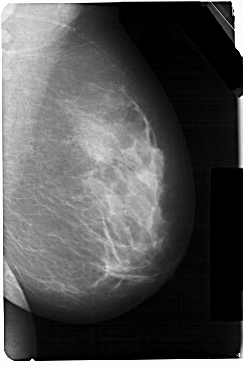

A_1301_1.RIGHT_MLO

RIGHT_MLO LINES 5491 PIXELS_PER_LINE 3631 BITS_PER_PIXEL 12 RESOLUTION 43.5 NON_OVERLAY